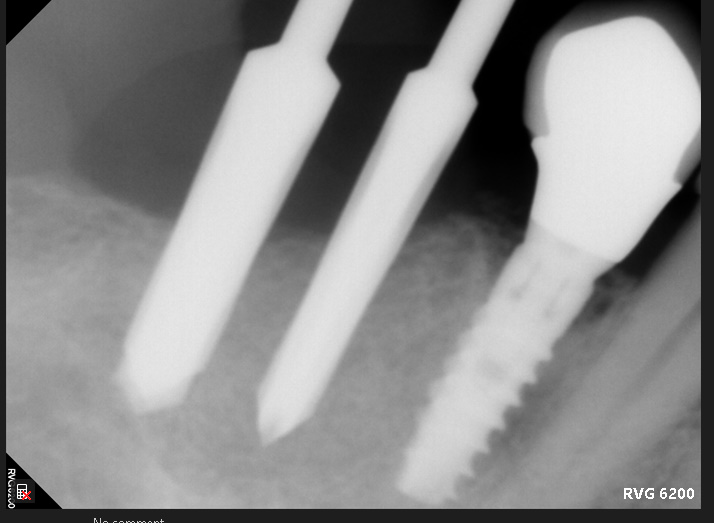

Upper left maxilla with deficient vertical&horizontal bone volume case